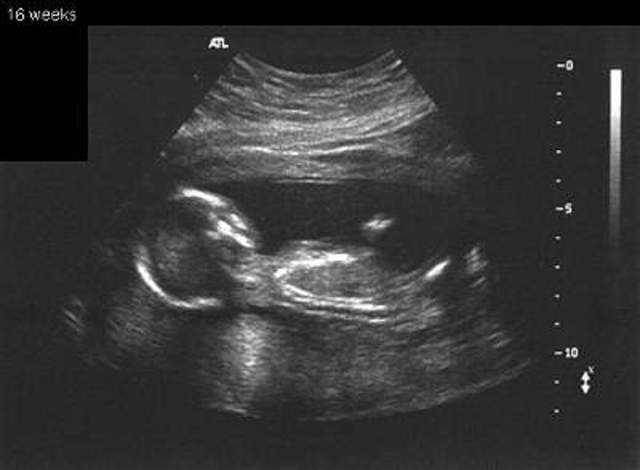

• 16 weeks

16 weeks

. Right now, he's about the size of an avocado: 4 1/2 inches long (head to rump) and 3 1/2 ounces. His legs are much more developed, his head is more erect than it has been, and his eyes have moved closer to the front of his head. His ears are close to their final position, too.